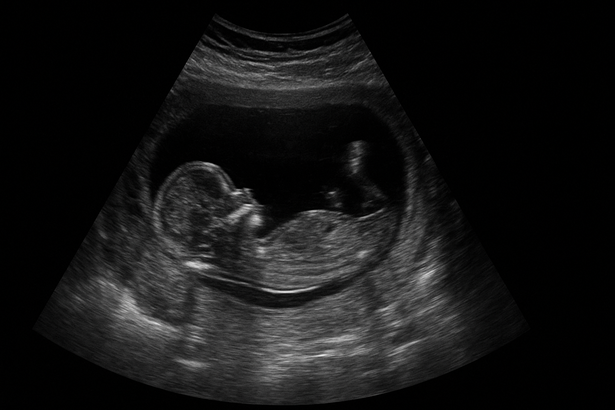

10 haftalık gebelik ultrason muayenesiyle bebeğin kalp atışı ve temel organ gelişimi değerlendirilebilir. Gebelikte tarama işlemleri planlanmaya başlanır.

10 haftalık gebelik kalp atışı seslerinin duyulabildiği bir dönemdir. Trimesterde kalp, dakikada 180 defaya kadar atabilir. Rutin muayenelerde kan tahlilleri ve ultrason kontrolleri yapılır.

Bebeğin kalp atışı ve genel gelişimi ultrason ile kontrol edilir.

Genellikle 10. haftada kalp atışı ultrason yoluyla tespit edilebilir.

10 haftalık gebelikte ultrason yapılır mı?

Rutin kontroller yoluyla bebek gelişimi takip edilir ve ek planlamalar yapılabilir.